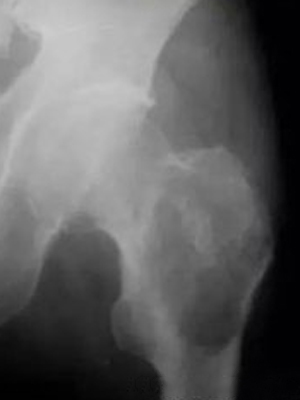

骨膜反应图 (49)

骨膜反应图 (48)

骨膜反应图 (47)